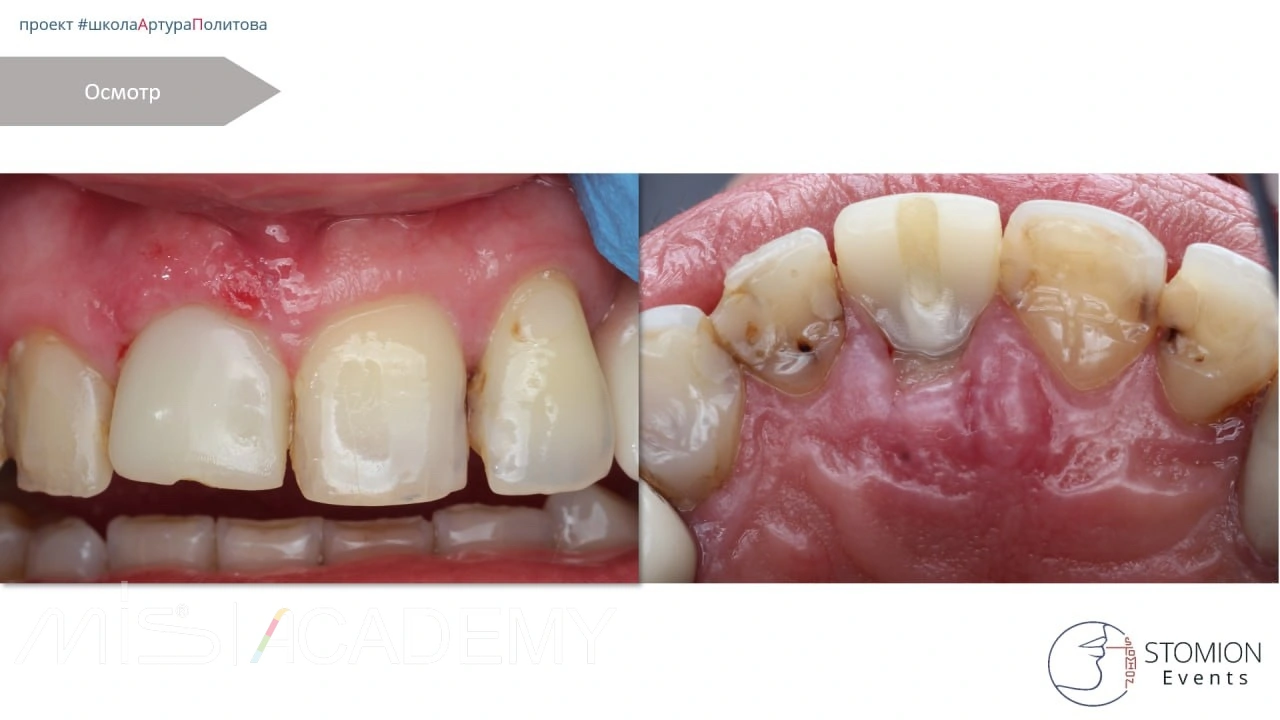

Снятие швов — через 9 суток.

Через 1 год — финишная ортопедическая реставрация на имплантате с уровня коннекта.